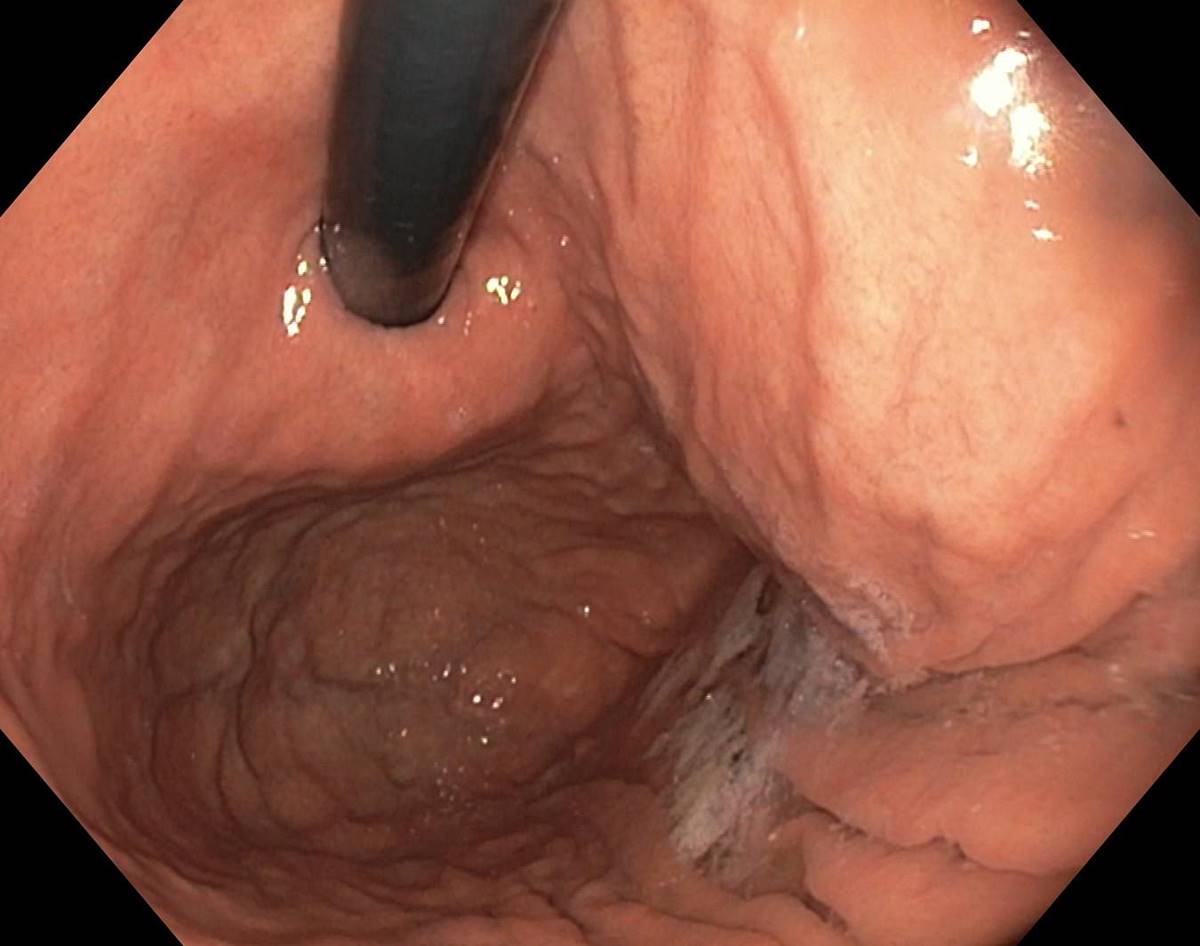

A Normal Gastric Fundus

A normal gastric fundus. Just click on a picture!

Diverticulum in the gastric fundus